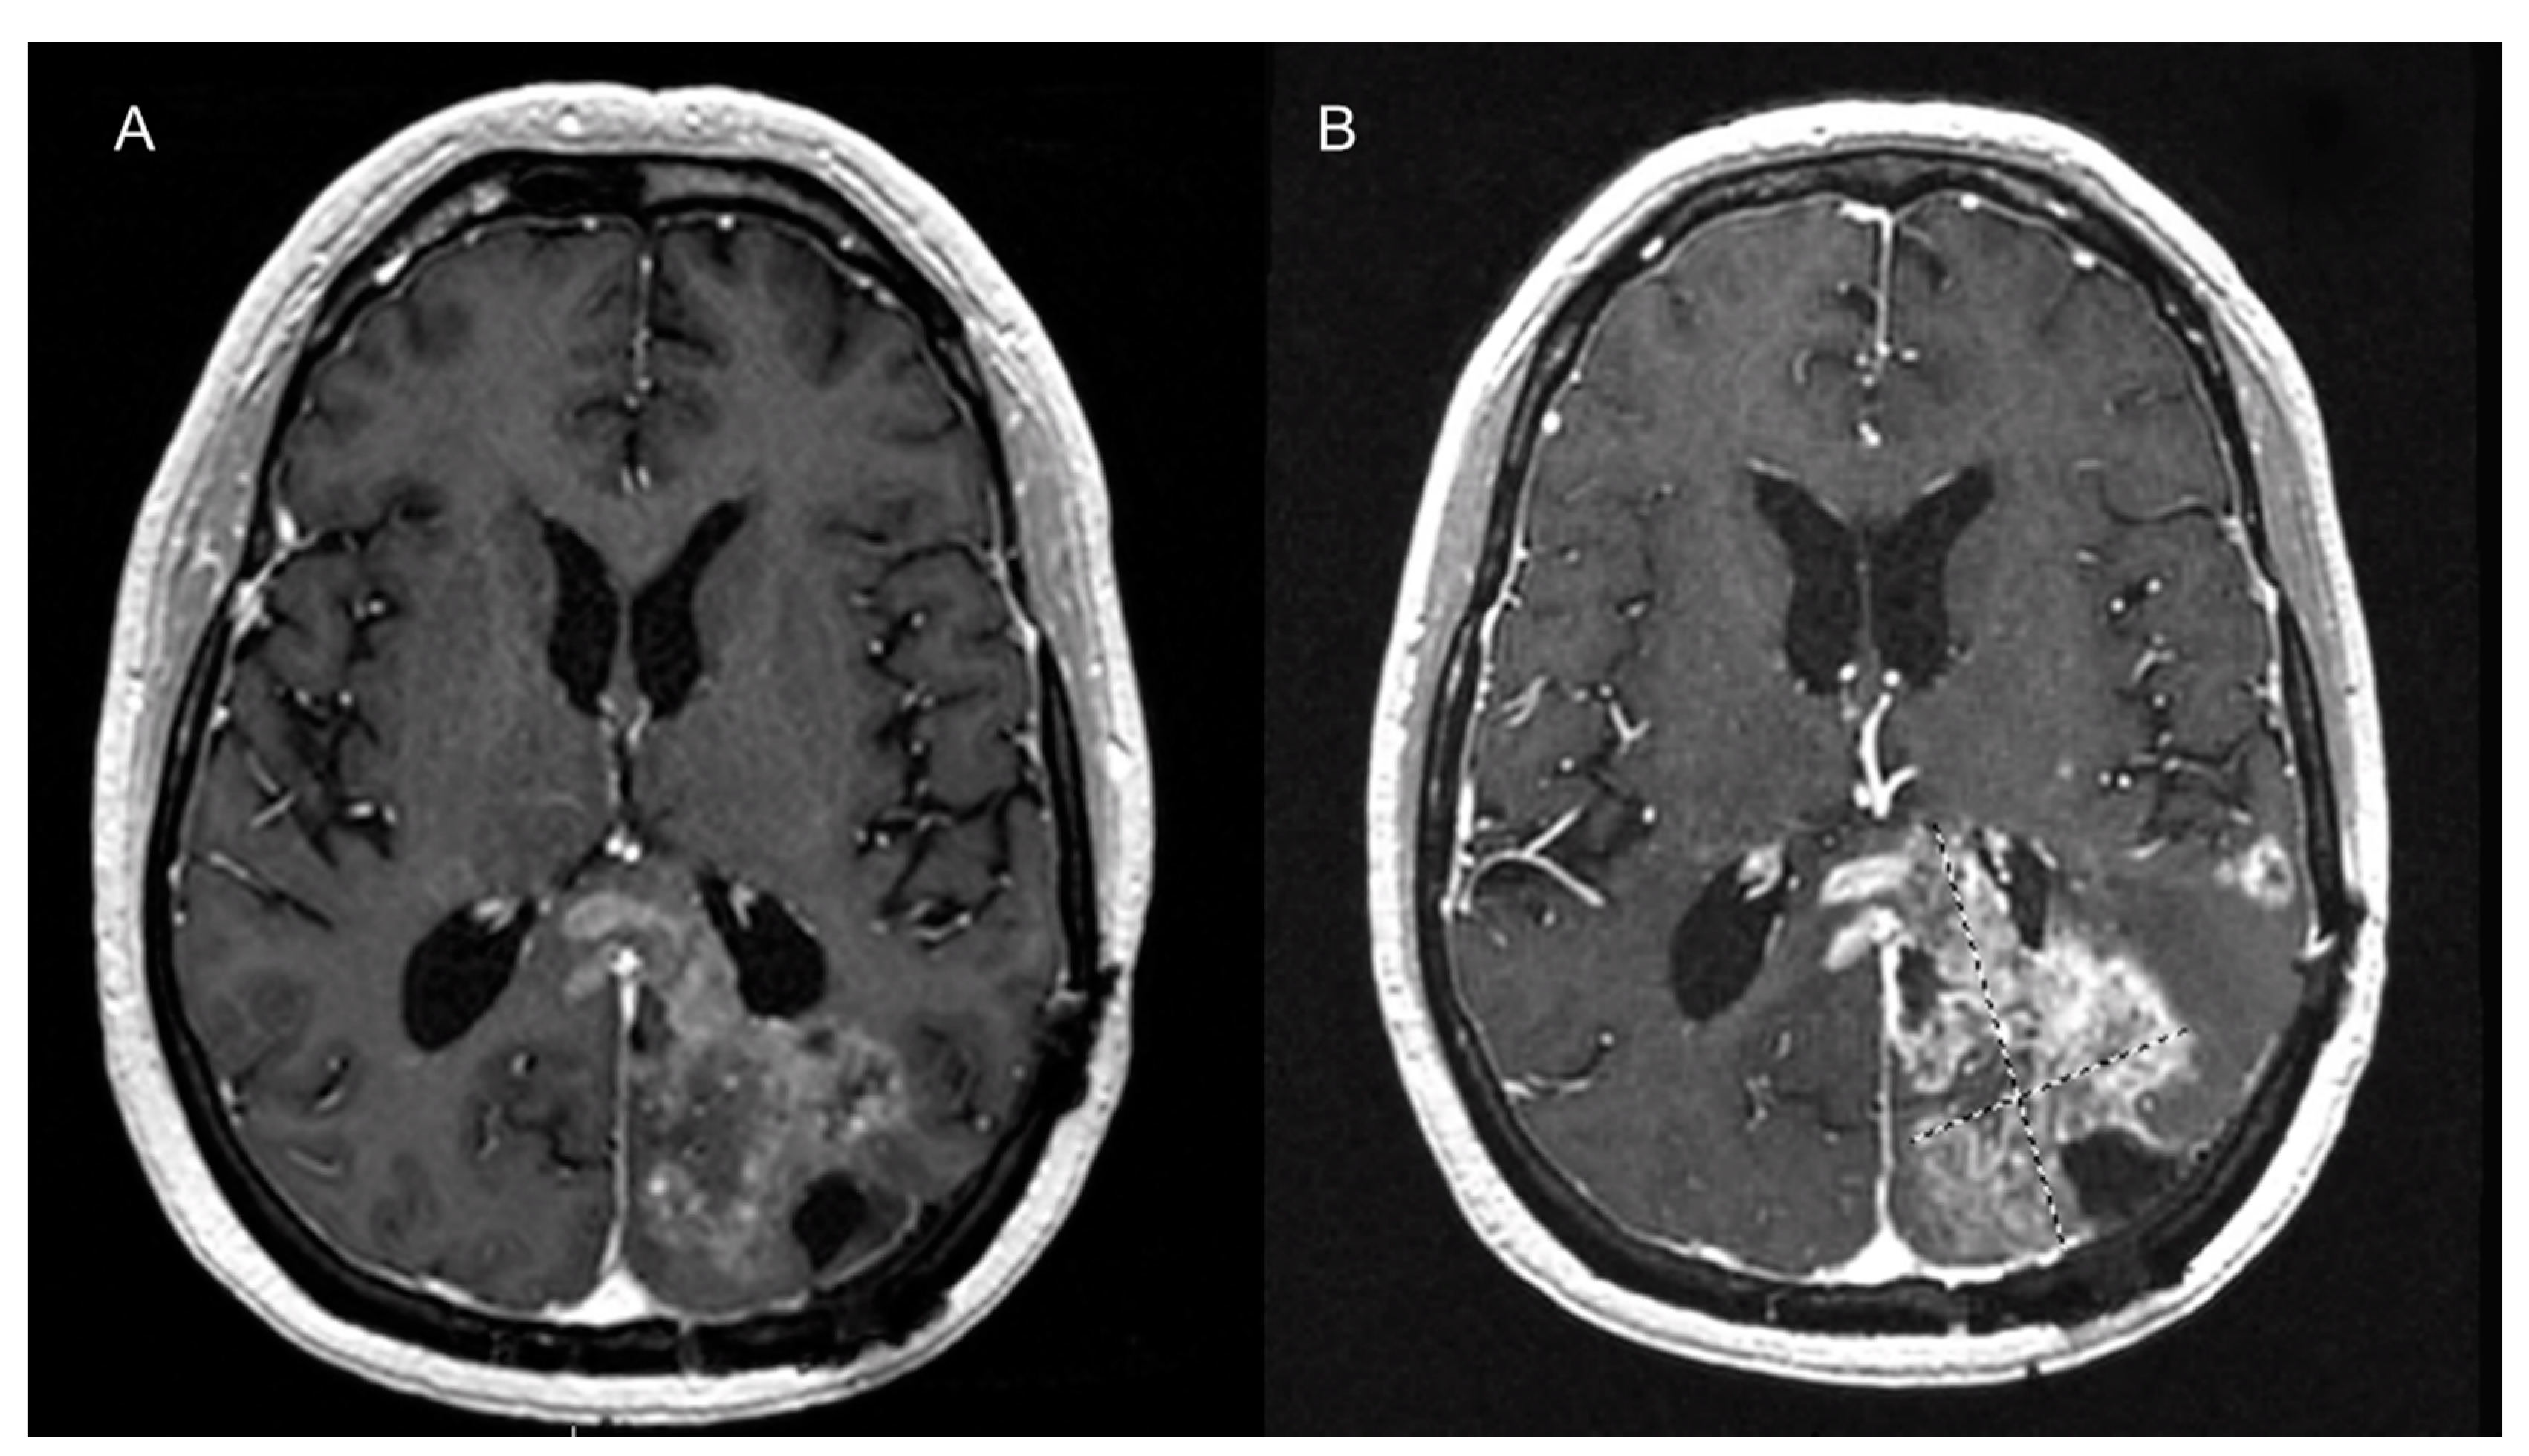

7.3. Dynamic Susceptibility Contrast (DSC) Perfusion MRI

7.4. Dynamic Contrast-Enhanced Perfusion MRI